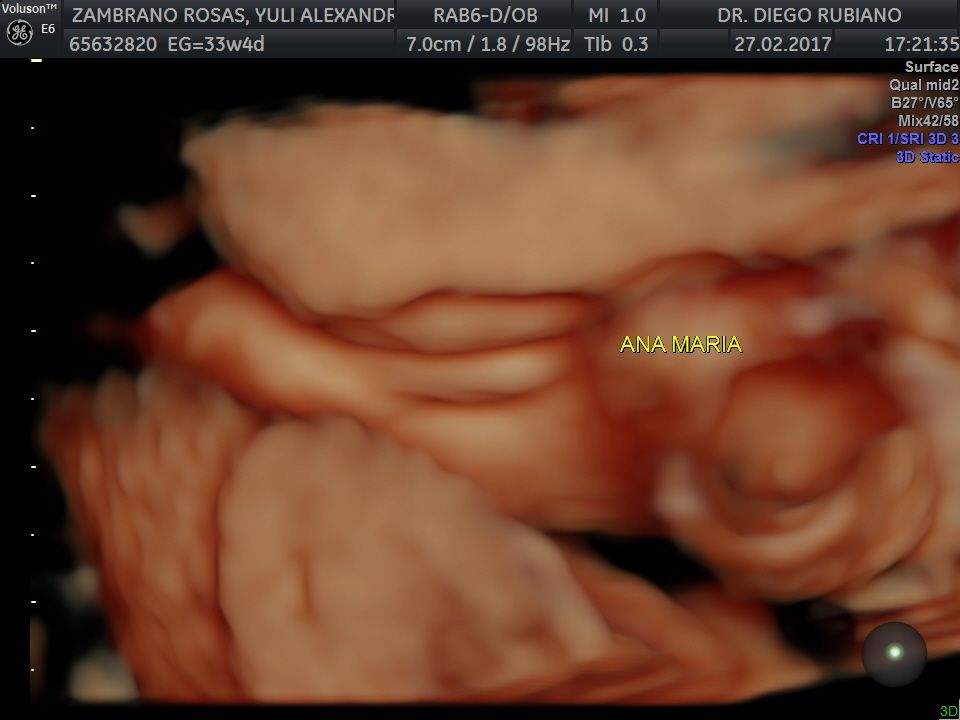

Fotos y videos

En nuestro consultorio médico, ofrecemos ecografías ginecológicas y obstétricas. Las ecografías ginecológicas son vitales para el control de la salud en mujeres no embarazadas, ayudando a detectar problemas temprano. Para futuras mamás, realizamos ecografías en todas las etapas del embarazo, utilizando equipos de alta tecnología para garantizar un seguimiento preciso del desarrollo del bebé. Ya sea que estés embarazada o no, nuestro servicio de ecografía está diseñado para cuidar de tu salud y bienestar.

• Consultorio privado Ecografía 3D  •